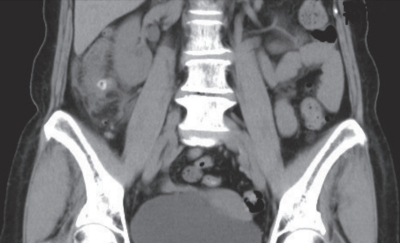

血液所見:赤血球 476万、Hb 15.3 g/dL、Ht 43%、白血球 12,400(好中球 75%、好酸球 1%、好塩基球 1%、単球 4%、リンパ球 19%)、血小板 25万。血液生化学所見:AST 34 U/L、ALT 60 U/L、尿素窒素 12 mg/dL、クレアチニン 0.9 mg/dL。CRP 3.6 mg/dL。腹部単純CTを別に示す。

この画像所見から最も考えられる疾患はどれか。

e. 大腸憩室炎